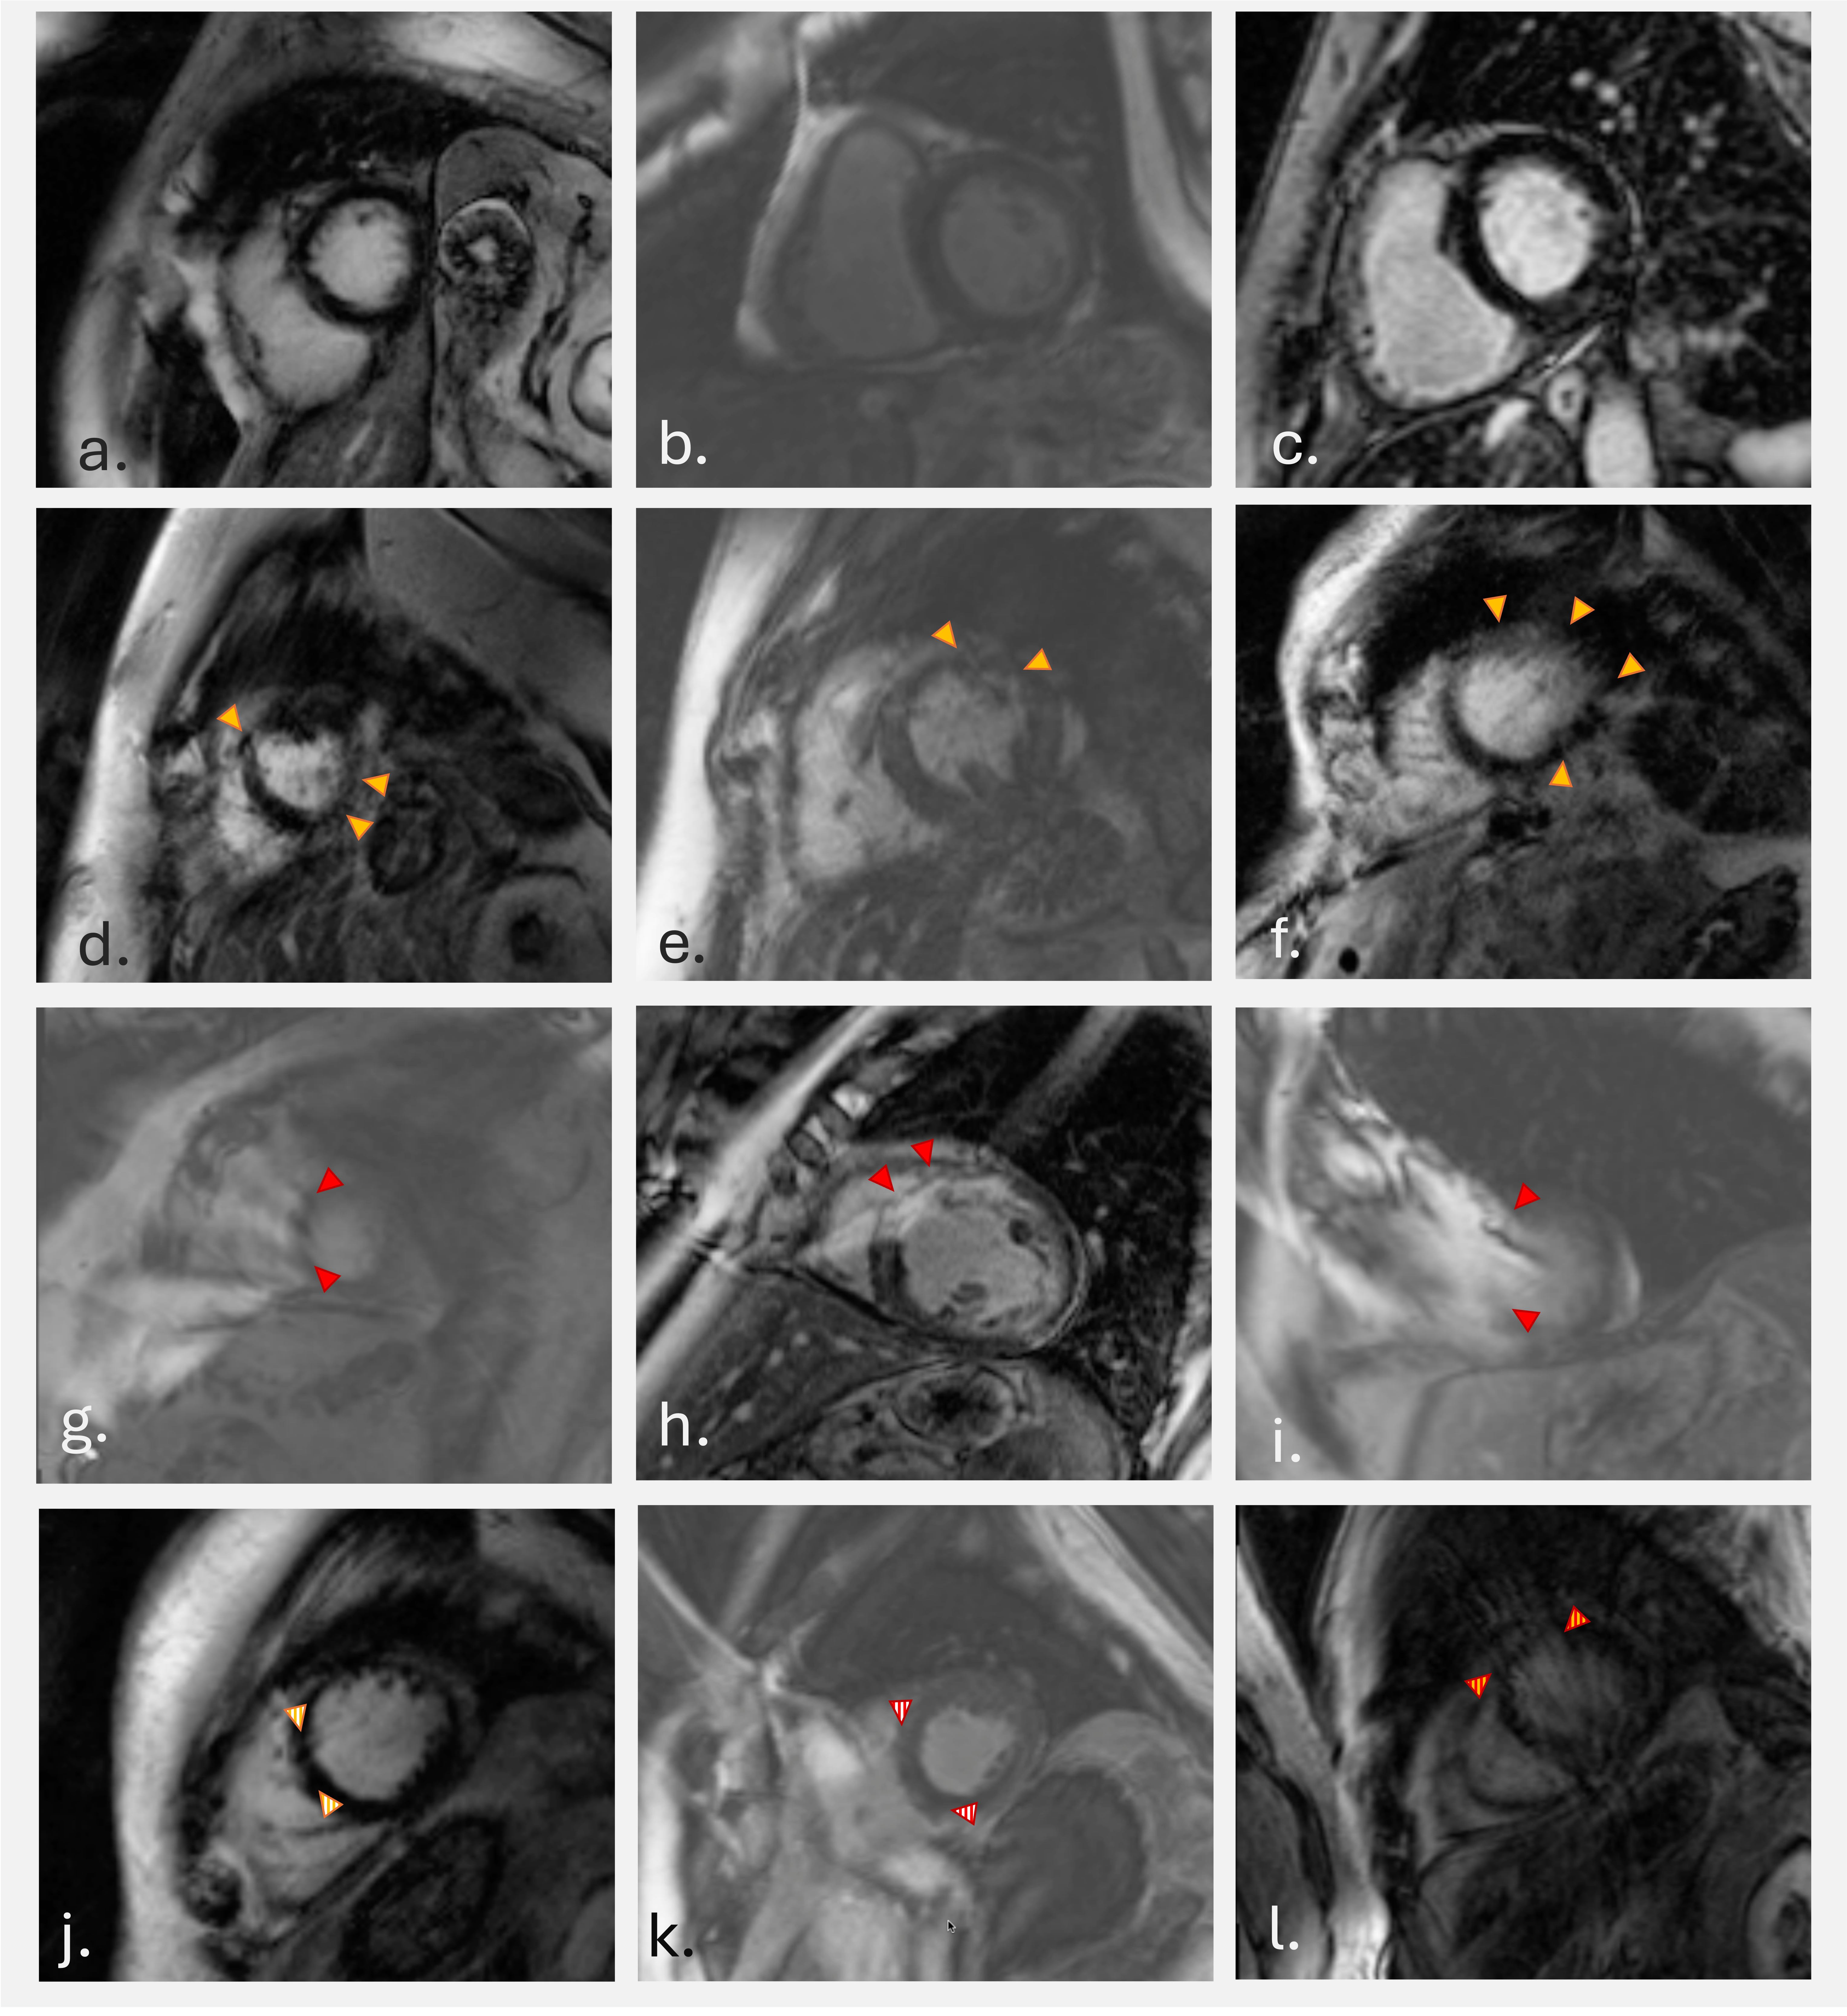

Figure 2: Label distribution by number of images per class and reader.

Figure 3: Resulting mean recall in percent for the nine CNNs. Scenario i) shows the binary classifier for ‘no artifact’ vs ‘artifact’, scenario ii) shows the classifier for differentiating ‘no artifact’ from ‘infolding’ and scenario iii) the multi-label approach for ‘no artifact’, ‘infolding’ and ‘motion’. The letter at the CNN indicates on which labels the CNN was trained and validated, the different columns provide which labels were used for testing the CNN. The two lower rows in the three subfigures show how reader A performed compared to ground truth labels B and vice versa for all scenarios. Note that the inter-reader mean recall of reader A and reader B for scenarios i) and iii) is similar to the performance of CNNA and CNNB respectively — that is, CNNA is compared to reader A, and CNNB to reader B. However, in scenario ii), CNNA outperforms reader A, and CNNB outperforms reader B when classifying infoldings versus artefact-free images, even though both CNNs were trained on labels from the respective human reader..png)